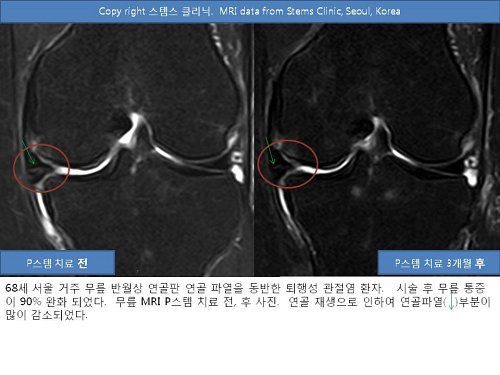

박재우 박사는 이 연골재생 결과를 무릎 반월상연골파열 환자에게도 적용해, 현재 비수술적인 방법으로 연골파열 환자들을 활발하게 치료 중이다. 무릎 반월상연골파열은 젊은 연령대에서는 무리한 운동이나 외상, 중장년층에서는 퇴행성관절염 때문에 점차 흔해지고 있는 질환이다. 반월상연골판은 무릎 관절에 가해지는 충격을 흡수하는 쿠션 구실을 하며 관절뼈와 연골을 보호하고, 무릎관절의 윤활기능 등도 담당한다. 반월상연골판 연골이 파열되면 관절내시경 수술로 손상된 부위을 절제, 제거해 무릎통증을 빨리 치료할 수 있지만 무릎관절에 필요한 연골을 없애는 것이어서 퇴행성관절염을 조기에 초래할 수 있고 또 슬개골연골연화증도 우려할 수 있다. 자가지방 줄기세포, PRP 시술은 이러한 단점을 보안한 치료라고 볼 수 있는 것이다.